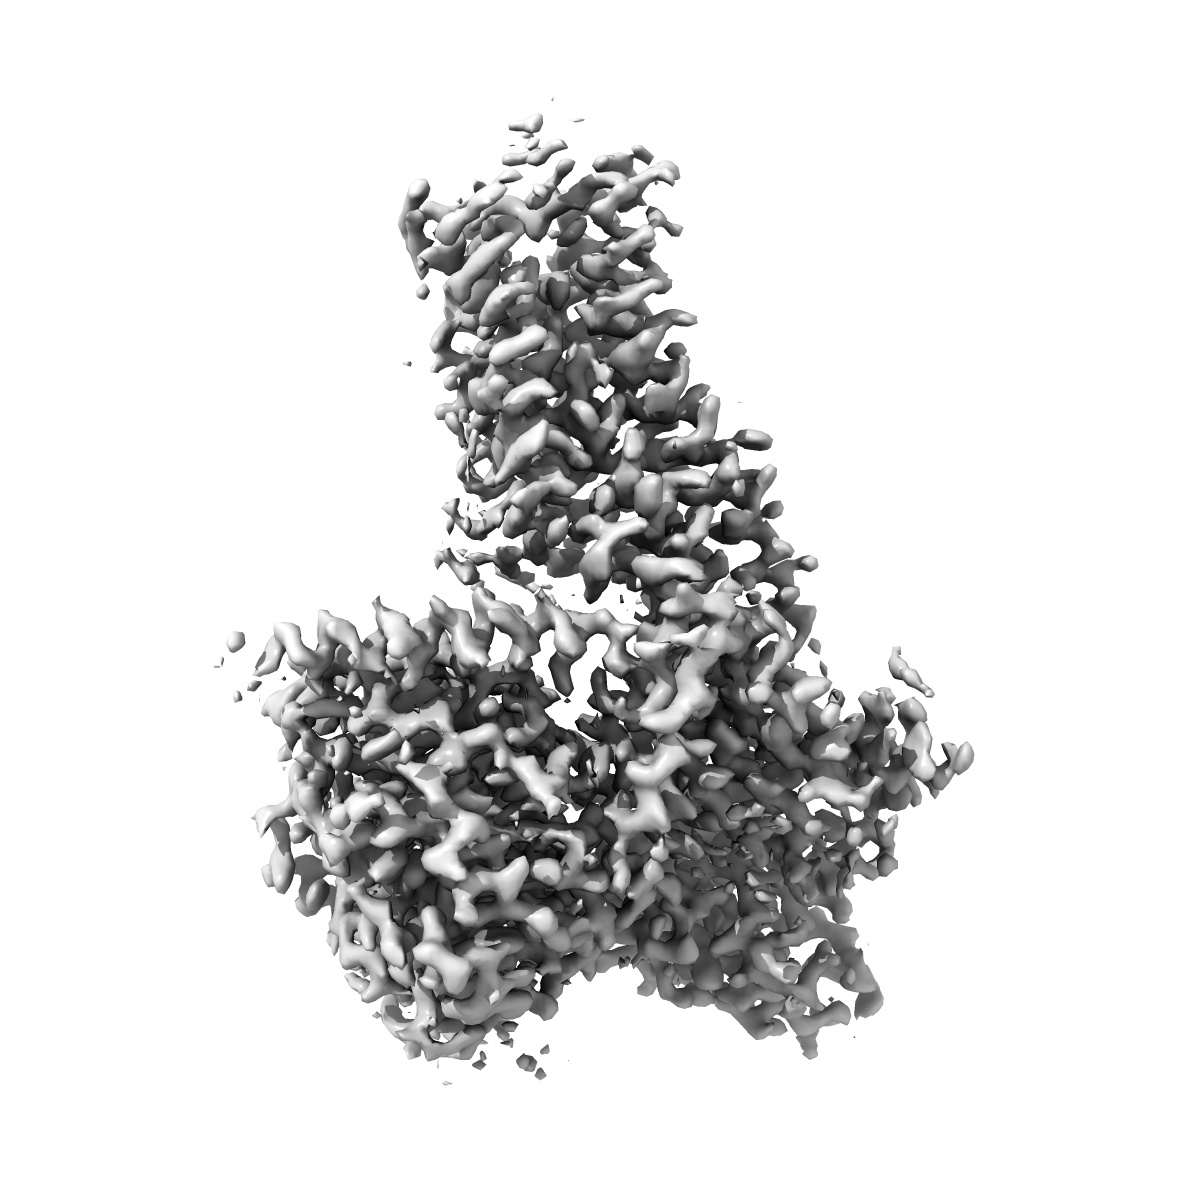

Cryo-EM structure of the METH-bound hTAAR1-Gs complex

Sample: METH-bound hTAAR1-Gs complex

Molecular Mechanisms of Methamphetamine-Induced Addiction via TAAR1 Activation.

Lin Y , Wang J, Shi F, Yang L, Wu S, Qiao A, Ye S

(2024) J Med Chem , 67 , 18593 - 18605